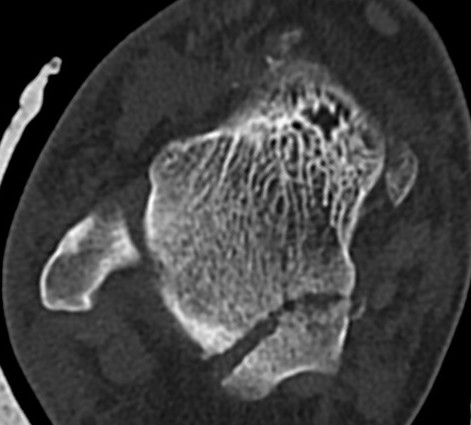

Fibular fracture and subtalar loose bodies after lateral subtalar dislocation

CT post reduction

Ensure

- congruent reduction

- look for fractures of talus / calcaneum

- look for intra-articular fragments